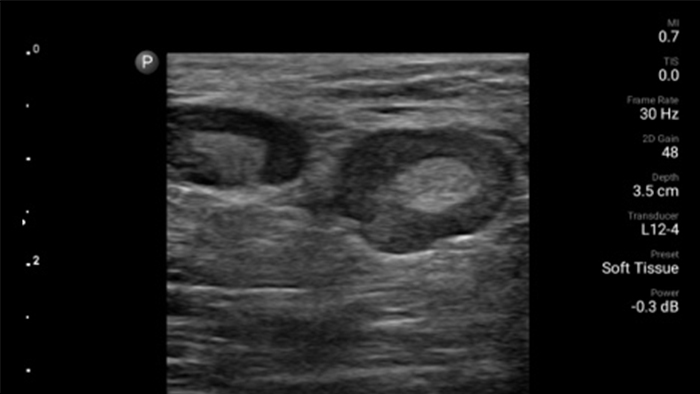

Lumify handheld ultrasound offers images that enhance diagnostic confidence.

See more when it counts

Lumify can help you make real-time decisions with more confidence, from assessment to recovery. Reveal the subtle details of an image, uncover enriched tissue definition with multiple angles and much more.